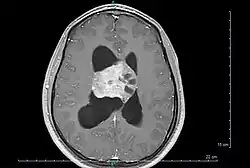

Центральная нейроцитома

Центральная нейроцитома — чрезвычайно редкая, обычно доброкачественная внутрижелудочковая опухоль головного мозга, которая обычно образуется из нейрональных клеток прозрачной перегородки.[1] Большинство центральных нейроцитом прорастают внутрь в желудочковую систему. Это приводит к двум основным неврологическим симптомам: нечеткости зрения и повышению внутричерепного давления. Лечение центральной нейроцитомы обычно включает хирургическое удаление с вероятностью рецидива примерно в 1 из 5 случаев.[2] Центральные нейроцитомы классифицируются как grade II опухоли в соответствии с классификацией опухолей нервной системы ВОЗ.[3][4]

Центральные нейроцитомы обычно располагаются супратенториально в боковом желудочке(боковых желудочках) и/или третьем желудочке. Наиболее частым местом является передняя часть одного из боковых желудочков с последующим распространением в другой боковой и третий желудочки. Вовлечение прозрачной перегородки вероятно является особенностью опухоли.[9] Изолированное поражение третьего и четвертого желудочков встречается редко.[10]